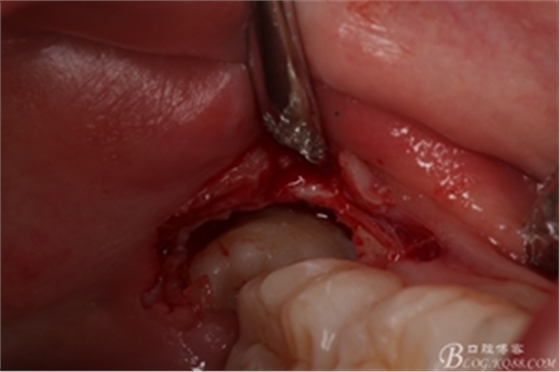

圖8. 翻瓣:建議翻小瓣

圖9.翻開瓣,可見38部分牙冠暴露

圖10. 翻開瓣。38牙冠還有部分骨質(zhì)覆蓋,遂用高速牙鉆去骨